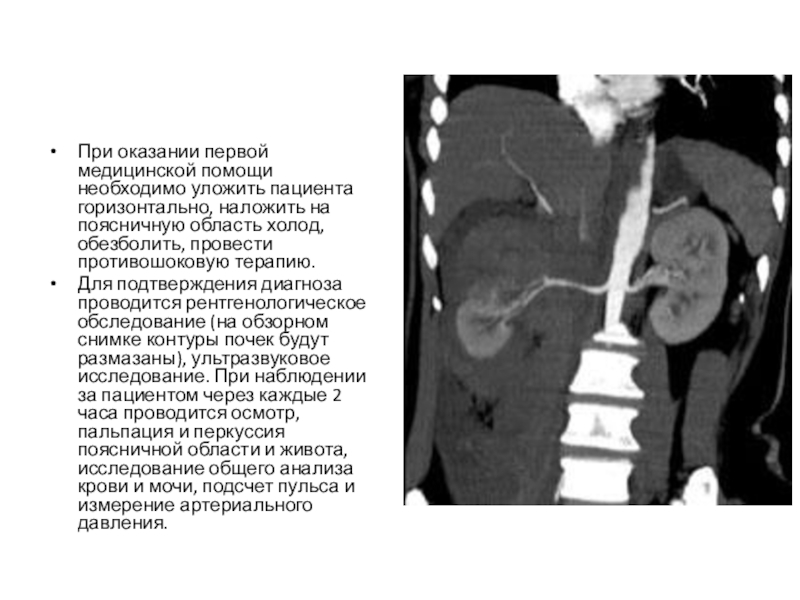

Слайд 44При оказании первой медицинской помощи необходимо уложить пациента горизонтально, наложить на

поясничную область холод, обезболить, провести противошоковую терапию.

Для подтверждения диагноза проводится рентгенологическое обследование (на обзорном снимке контуры почек будут размазаны), ультразвуковое исследование. При наблюдении за пациентом через каждые 2 часа проводится осмотр, пальпация и перкуссия поясничной области и живота, исследование общего анализа крови и мочи, подсчет пульса и измерение артериального давления.